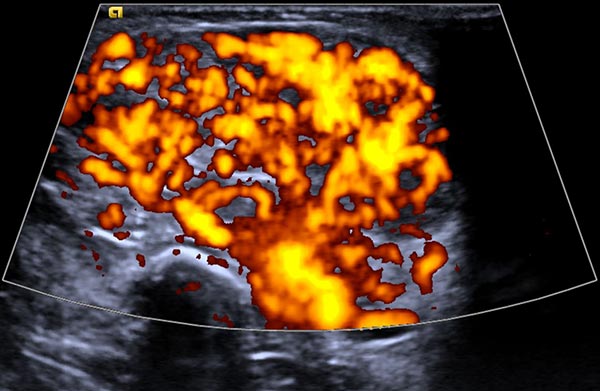

In der Power-Dopplersonographie zeigt sich eine starke Perfusion der Raumforderung, sodass von einem vaskulären Tumor ausgegangen wird. Die starke Blutströmung wird hier orange im B-Bild dargestellt, die Strömungsrichtung ist dabei nicht farbkodiert.

Die Power-Dopplersonographie Ende des 8. Lebensmonats zeigt nicht nur eine Volumenzunahme des subkutanen Tumors, sondern auch eine nochmals stark gesteigerte Perfusion (orange farbkodiert).